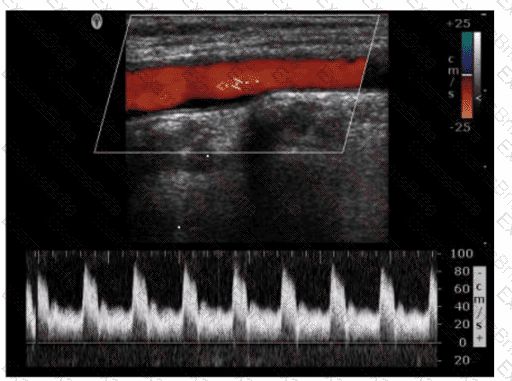

Questions 26

Which pulsed-wave Doppler adjustment would be appropriate to correct the aliasing seen in this image?

Options:

A.

Increase the spectral Doppler gain.

B.

Decrease the spectral Doppler gain.

C.

Increase the Doppler pulse repetition frequency.

D.

Decrease the Doppler pulse repetition frequency.

Discussion 0